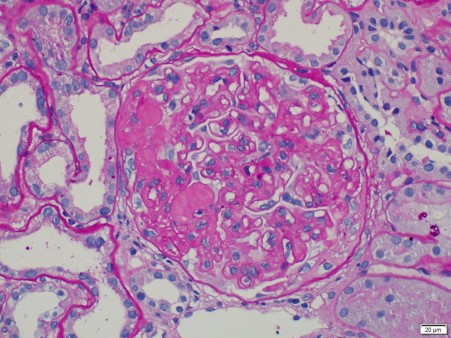

肾穿刺活检:1.肾小球微血管病变,考虑可能和仑伐替尼相关;2.合并糖尿病肾病 3.肾小动脉硬化。

图1. 肾穿刺活检光镜下病理表现

诊断方法 入院后完善相关检查,排除禁忌后行肾穿刺活检术,病理示肾小球微血管病变(考虑可能和仑伐替尼相关)合并糖尿病肾病及肾小动脉硬化。